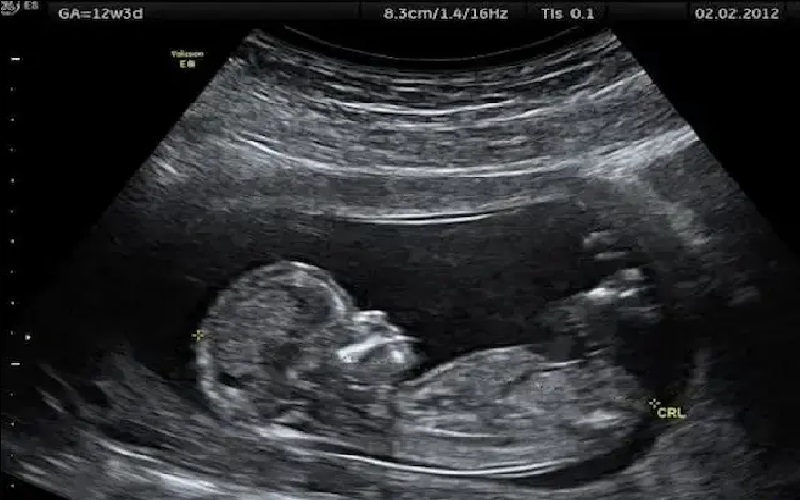

يؤكد الأطباء أن التصوير بالموجات فوق الصوتية أداة تشخيصية أساسية لمراقبة نمو الجنين وصحة الأم طوال فترة الحمل، وليس فقط لمعرفة نوع الجنين.

وتعتمد هذه التقنية على موجات صوتية عالية التردد وليس الإشعاع، ما يجعلها آمنة حتى للنساء ذوات الحمل منخفض الخطورة.

ويُتيح الفحص تقييم دماغ الجنين، القلب، الصدر، البطن والأطراف بدقة عالية، رغم أن بعض الحالات قد لا تظهر إلا لاحقاً أو تحتاج لتصوير إضافي مثل الرنين المغناطيسي للجنين.